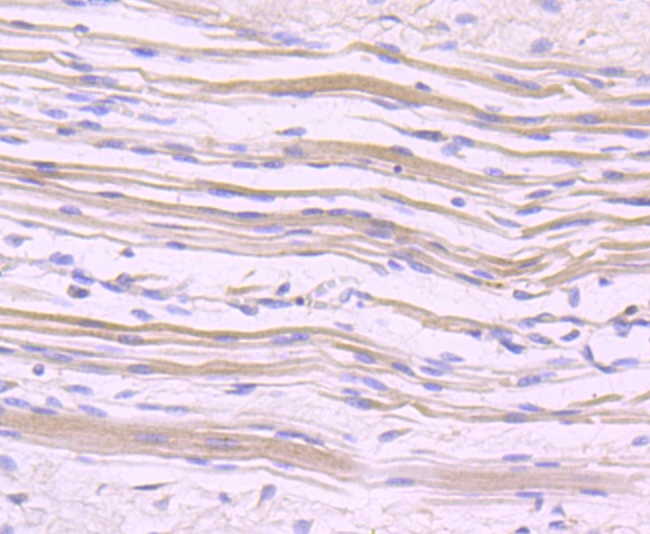

Immunohistochemical analysis of paraffin-embedded human skeleton muscle tissue using anti-NFAT2 antibody. Counter stained with hematoxylin.